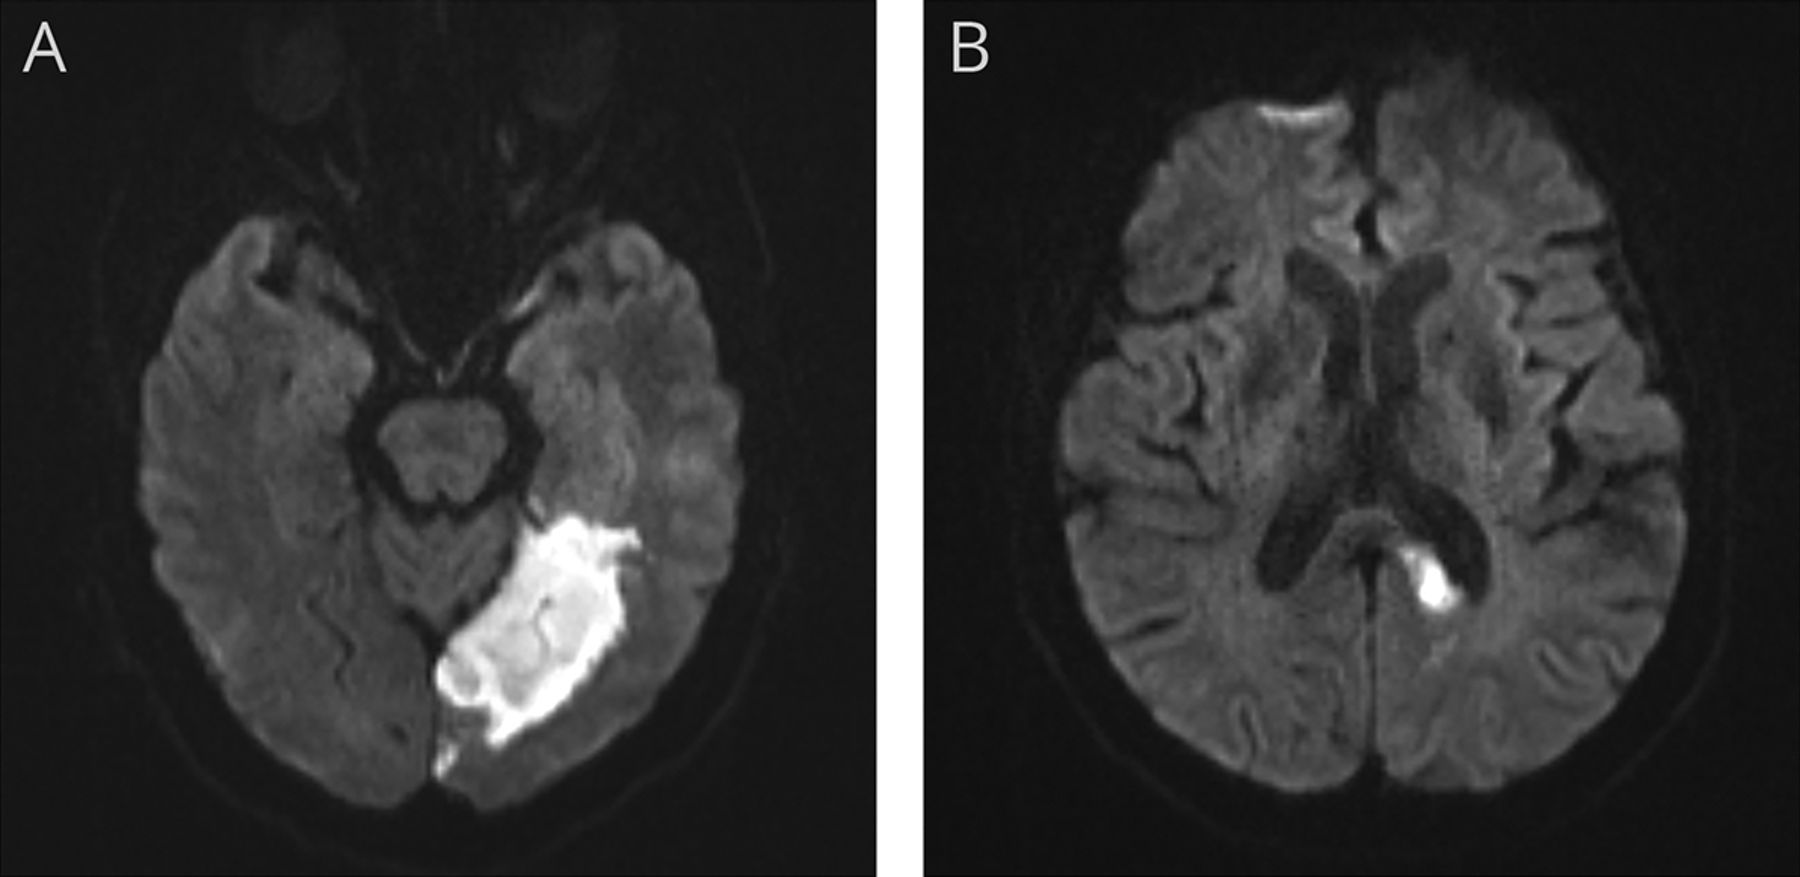

一个64岁的有文化的中国人面对突然发生的阅读困难。检查发现右同音异义的偏盲和纯失读症。口服阅读测试表明,他经常读一个字符与另一个类似的形状但不同的含义和发音(图1)。脑部MRI显示急性梗死涉及左枕叶、颞叶,胼胝体压部(图2)。纯失读症是临床分离综合征在患者第一次描述了类似的梗死Dejerine于1892年。1造型酷似错误可能是中国纯失读症现象的特点。